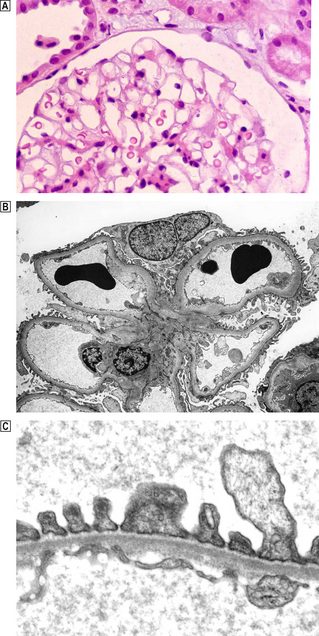

Glomerular structure and function

The formation of urine begins in the glomeruli, where the filtration of approximately 800 litres of plasma each day results in 140–180 litres of filtrate, most of which is reabsorbed by the tubules. Each glomerulus comprises a tuft of capillaries projecting into Bowman’s space (Fig. 21.1A).

image

Fig. 21.1 Normal glomerulus. image Each glomerulus consists of capillaries invested by epithelial cells and is surrounded by Bowman’s space. image Low-power electron micrograph showing capillary loops clustered around the mesangium. The basement membrane does not surround the capillary loop completely but is reflected onto the adjacent loop in the region of the mesangium, leaving the mesangial area covered only by the endothelium. image High-power electron micrograph showing ultrastructure of the glomerular capillary. The wall of each glomerular capillary comprises an inner thin layer of fenestrated vascular endothelium, the basement membrane and an outer epithelial layer characterised by cytoplasmic (‘foot’) processes. Slit diaphragms span the gap between adjacent epithelial cells. In electron micrographs the basement membrane has a central dense zone, the lamina densa, surrounded on either side by the less densely packed lamina rara interna and externa.

The external aspect of the basement membrane bears epithelial cells with complex interdigitating cellular processes, termed foot processes, enveloping the capillary loops. Modified adherens-type junctions (filtration slit diaphragms) occur where the foot processes meet and are essential to the function of the epithelial cell (Fig. 21.1C). The integrity of the slit diaphragm is maintained by the complex inter-relationship of numerous proteins including nephrin, podocin and CD2-associated protein (CD2AP). Other proteins, such as integrins, span the membrane and anchor the actin cytoskeleton to the collagen IV in the lamina rara externa of the basement membrane. Therefore, changes in these proteins modify the configuration of the foot process, and defects in the genes encoding these proteins result in simplification of the foot processes.

The basement membrane is reflected over the mesangial area to extend onto the adjacent capillary, which means endothelium is attached to the mesangial matrix in the central core area (Fig. 21.1B). This allows access of immune complexes to the mesangium and the ability of mesangial cells to probe the capillary lumen.